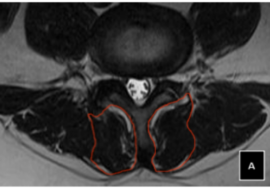

العمود الفقري لا يزال مرنًا: في هذه المرحلة، يمكن تعديل الانحناء بسهولة قبل أن تتشكل التغيرات البنيوية في الفقرات.

تمارين مخصصة: لتعزيز العضلات المحيطة بالعمود الفقري وتحسين التوازن.

الانحناءات الصغيرة في العمود الفقري بين 10 و25 درجة تمثل فرصة ذهبية للتدخل المبكر قبل أن تصبح التغيرات الهيكلية أكثر صعوبة في التصحيح. الدراسات الحديثة تؤكد أن أفضل النتائج تتحقق عند بدء العلاج في هذه المرحلة، سواء من خلال العلاج الطبيعي المخصص، تمارين تقوية العضلات، أو استخدام الحزام التصحيحي عند الحاجة.